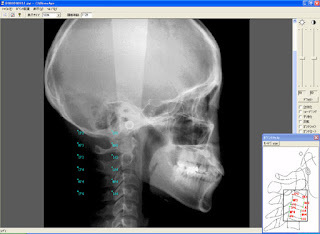

③レントゲン撮影

(パントモX線・頭部X線・頭部X線規格写真正面側面など)